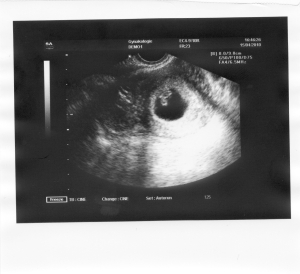

de dr azt mondta, hogy nem elég hosszúak a fájások, annak ellenére hogy a görbe már sinus görbe volt és nem csúcsos hegyet mutatott... Akkor jött az uhu, ott is rendben volt minden, már az anesztessel is beszéltem!!! Nagyon kedves dr bácsi volt! és akkor közli a dr, hogy felvenne... Mondom nemár, anyáméknál van a gyerek, ahol a házban csak egy szál ágy árválkodik, költözés miatt, meg vasárnap át kell adnunk a házat... azt mondja jó, de este 7re vár vissza és ha egy picuri változás is van, akkor befekvés és gyerek.Hazaértünk, pihentem sokat, de a fájdalom miatt nem tudtam aludni. Aztán vissza, de ekkor már csak 10-12 percenként jöttek a fájdalmak. Már örültem előre